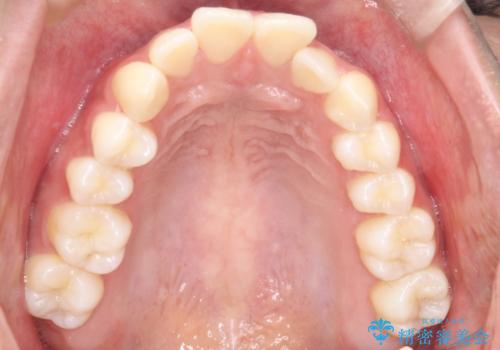

3. 【審美ワイヤー】口元を下げたいの治療後